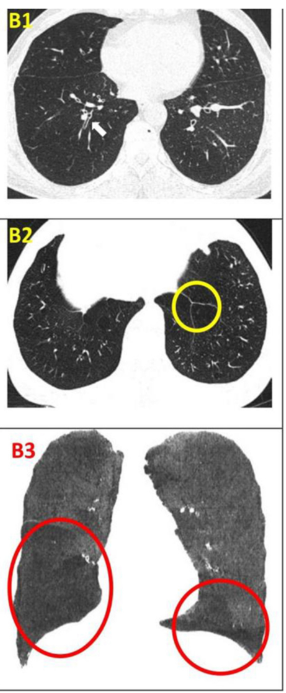

影像學(xué)檢查:對(duì)于患者 #2902,定量分析顯示基線時(shí)總體肺氣腫面積比為 12.75%,移植后 24 周降至 10.02%。在患者 #8009 中,肺氣腫面積比值從基線的 10.85% 下降到移植后 12 周的 9.08%。CT 圖像的三維可視化顯示,肺氣腫的減輕在下葉比在上葉更明顯。

影像學(xué)檢查:隨訪12個(gè)月時(shí),定量胸部CT掃描示患者吸入總肺容積略有增加,肺氣腫指數(shù)無明顯變化。支氣管壁厚度(WT)的變化以WT、壁面積(WA)及WA百分比(%WA)的減少,以及支氣管內(nèi)徑(ID)和管腔面積(LA)的增大來評(píng)估。

干細(xì)胞治療一年后,雙肺RB1和RB10的WT均減少,LA增加(粗體指數(shù))。